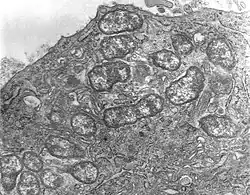

Scrub typhus or bush typhus is a form of typhus caused by the intracellular parasite Orientia tsutsugamushi, a Gram-negative α-proteobacterium of family Rickettsiaceae first isolated and identified in 1930 in Japan.[2][3]